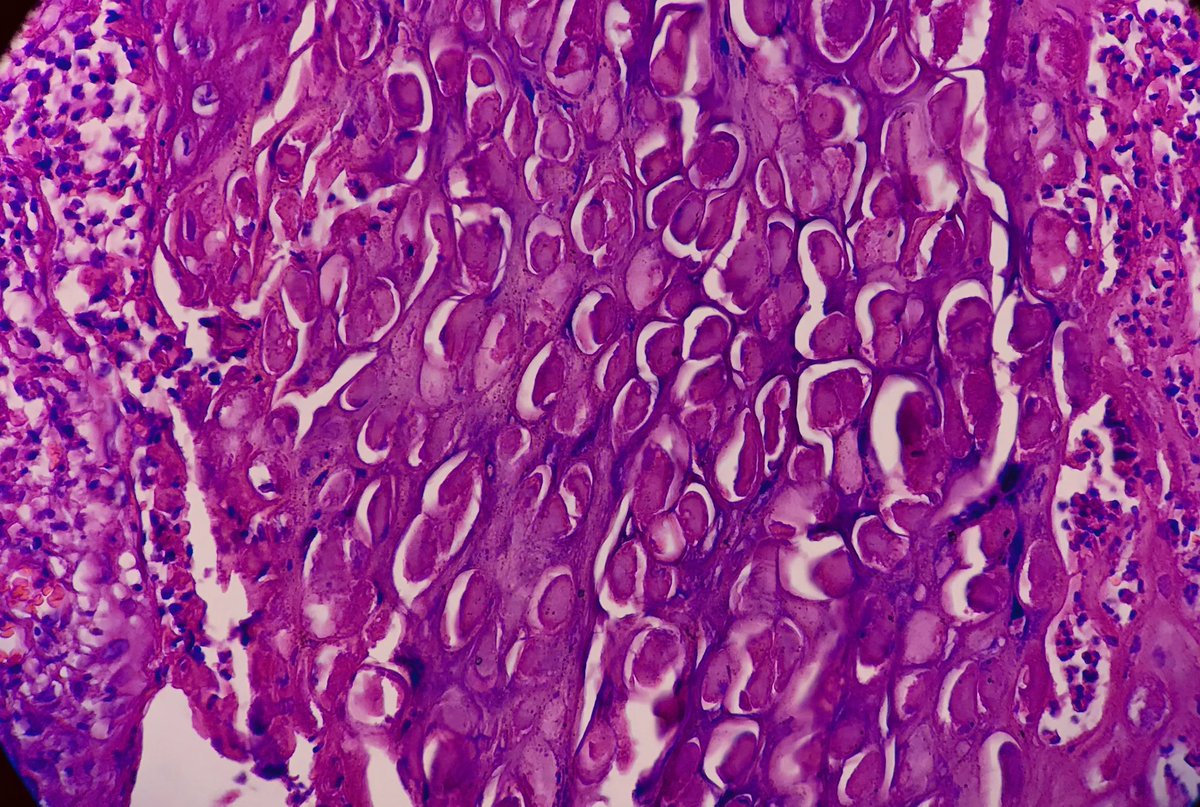

A 34-year-old woman with genital skin lesion Dx: Molluscum Contagiosum Henderson-Patterson bodies #Pathology😍 #Tums #PathTwitter

A 34-year-old woman with genital skin lesion

Dx: Molluscum Contagiosum

Henderson-Patterson bodies

#Pathology😍

#Tums #PathTwitter